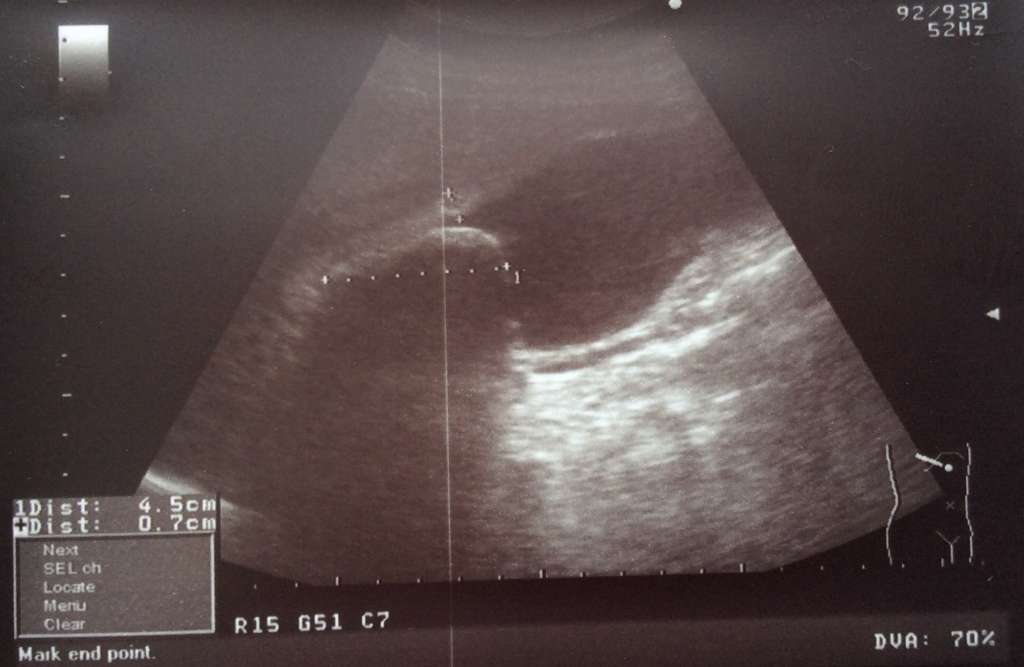

УЗИ ЖКБ Острый калькулезный флегмонозный холецистит фото